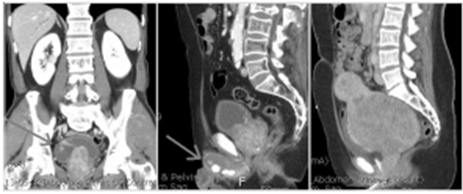

예시 2) 54세 남자환자, Rt. flank pain, hematuria를 주소로 응급실 내원

사진설명: 좌측 사진은 전형적인 ureter stone 소견이다.

URSL 시행당시 요관벽의 부종 및 염증 소견이 보인다. 조직검사상 urotheilal carcinoma (TCC high grade) 소견이 보였고 washing cytology에서 비정상세포의 모습이 보였다.